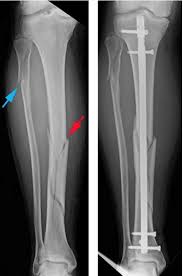

Spiral fractures are usually the result of high energy trauma and are likely to be associated with. Summary summary (text) medline pmcid list. A fracture, sometimes called a torsion fracture, in which a bone has been twisted apart. Spiral fractures often occur when the body is in motion while one extremity is planted. Spiral fracture — sagittarius a star 03:25. Detailed step by step desription of intramedullary nailing for simple fracture, spiral located in our module intramedullary fixation is valuable and appropriate for the majority of tibial fractures. Two spiral fractures sustained following only minor trauma. Meaning of spiral fracture medical term.

Two spiral fractures sustained following only minor trauma. Complete fractures are categorized based on the way the bone breaks. It occurs due to a rotational, or twisting, force. Try our newest study sets that focus on spiral fracture to increase your studying efficiency and retention. Detailed step by step desription of intramedullary nailing for simple fracture, spiral located in our module intramedullary fixation is valuable and appropriate for the majority of tibial fractures. Other articles where spiral fracture is discussed: A spiral fracture is a bone fracture occurring when torque is applied along the axis of a bone.1 spiral fractures often occur when the body is in motion while one extremity is planted. Spiral fracture femur (there is a significantly displaced spiral fracture of the proximal femoral. A spiral fracture, also known as torsion fracture, is a type of complete fracture. A spiral fracture is a bone fracture caused by a twisting force. A spiral fracture is usually treated right away with surgery. Summary summary (text) medline pmcid list. Know ways to lower your risks in the first place.

A fracture, sometimes called a torsion fracture, in which a bone has been twisted apart. Shiel jr., md, facp, facr. A spiral fracture is a bone fracture occurring when torque is applied along the axis of a bone. Other articles where spiral fracture is discussed: Summary summary (text) medline pmcid list. It occurs due to a rotational, or twisting, force. Detailed step by step desription of intramedullary nailing for simple fracture, spiral located in our module intramedullary fixation is valuable and appropriate for the majority of tibial fractures. Also called a torsion fracture, a spiral my son suffered a spiral femur fracture and the er doctor didn't report it.

Spiral fracture femur (there is a significantly displaced spiral fracture of the proximal femoral. A spiral fracture is usually treated right away with surgery. Summary summary (text) medline pmcid list. A spiral fracture is a bone fracture that occurs when a long bone is broken by a twisting force. Also called a torsion fracture, a spiral my son suffered a spiral femur fracture and the er doctor didn't report it. It occurs due to a rotational, or twisting, force. Detailed step by step desription of intramedullary nailing for simple fracture, spiral located in our module intramedullary fixation is valuable and appropriate for the majority of tibial fractures. Medical definition of spiral fracture. Spiral fractures are complete fractures of long bones that result from a rotational force applied to the figure 1. Spiral fractures are usually the result of high energy trauma and are likely to be associated with. Try our newest study sets that focus on spiral fracture to increase your studying efficiency and retention. Bone depressed fracture fractures simple fracture closed reduction. Finally, two days later, the other.